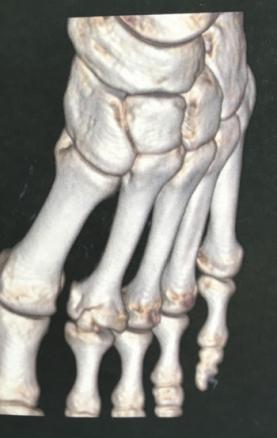

Après trois semaines de repos et la persistance de la douleur limitant la marche, un scanner est réalisé, qui montre une nécrose de la tête du 2e métatarsien (fig. 3).